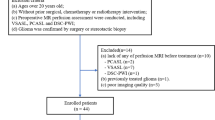

We included ten patients with a primary brain tumour who underwent awake brain surgery at the Department of Neurosurgery of Erasmus MC (Rotterdam, The Netherlands) and were included in the previously published fUS-study [14].

Patients’ eligibility for the fUS study has been reported earlier [14]. Additionally, the following inclusion criteria for this study were set, i.e., the availability of the DSC perfusion MRI scans and of the ultrafast Doppler ultrasound images. On this basis, three patients were excluded: patients #01 and #07 for missing DSC perfusion MRI scans and patient #06 due to technical issues with acquiring the ultrafast Doppler ultrasound images. Five out of the remaining seven included patients had simultaneously been included in a published study [15] (iGENE) which focused on evaluating the clinical potential of assessing tumour vasculature in the three different types of non-enhancing adult-type glioma with MRI. Patients’ clinical information was collected on age, sex, and histopathological and molecular diagnosis of the tumour.